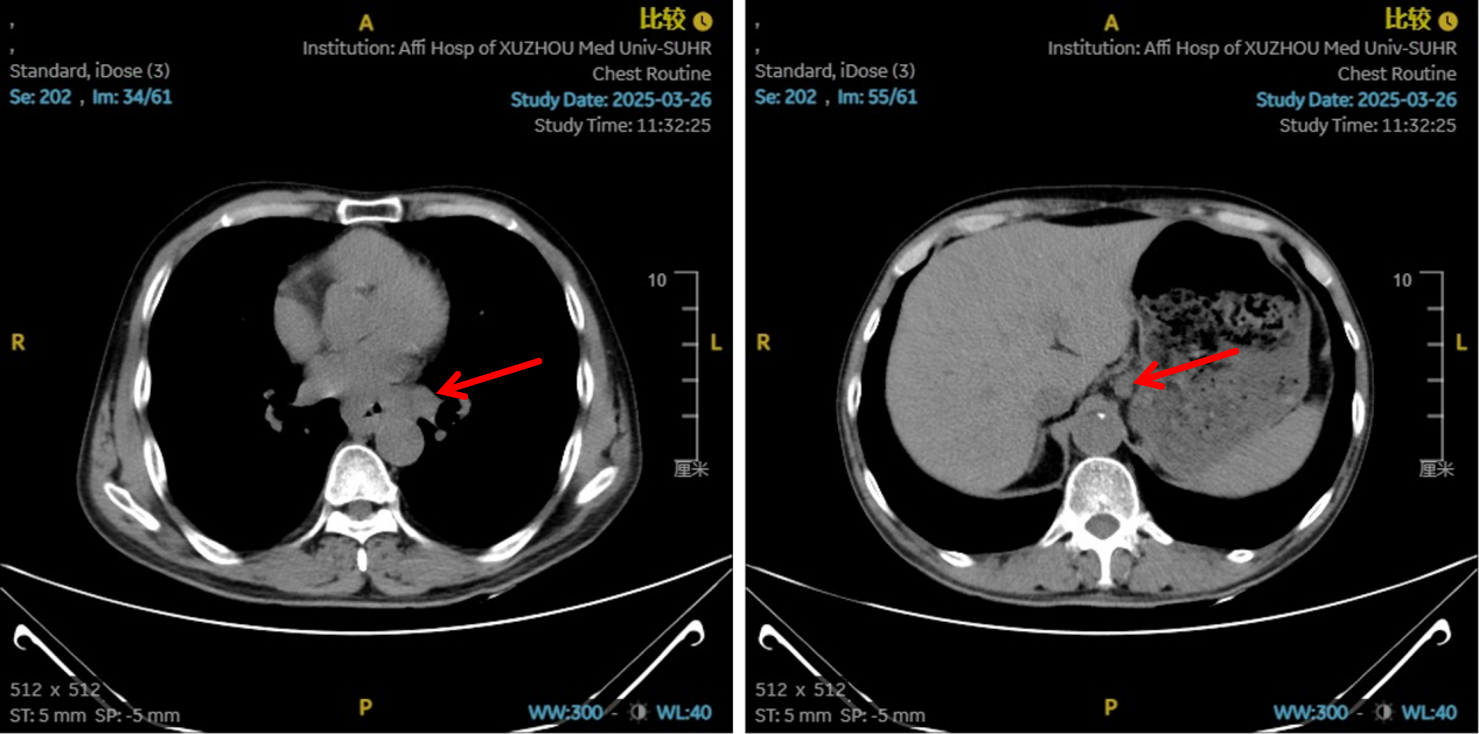

图5:4、6周期化免靶后食管癌病灶对比

图6:4、6周期化免靶后淋巴结对比

图7:4周期治疗后影像学 [图左:“食管Ca化疗后”,食管胸中下段管壁增厚,较厚处管壁约12mm,边缘模糊,病灶局部与邻近大血管、气管壁分界不清。图右:纵隔内(3P、4、7)、左肺门示稍大淋巴结影。]

图8:6周期治疗后影像学 [图左:“食管Ca化疗后”,食管胸中下段管壁增厚,较厚处管壁约10mm,边缘模糊,病灶局部与邻近大血管、气管壁分界不清。图右:纵隔内(3P、4、7)示小淋巴结影。]

疗效评估

治疗2周期后,食管壁厚度由17mm降至15mm,淋巴结由18mm×15mm缩小至16mm×13mm;4周期后,食管壁进一步缩至12mm,淋巴结明显减少;6周期后,食管壁仅余10mm,纵隔内仅见小淋巴结影,疗效评估“接近CR”。